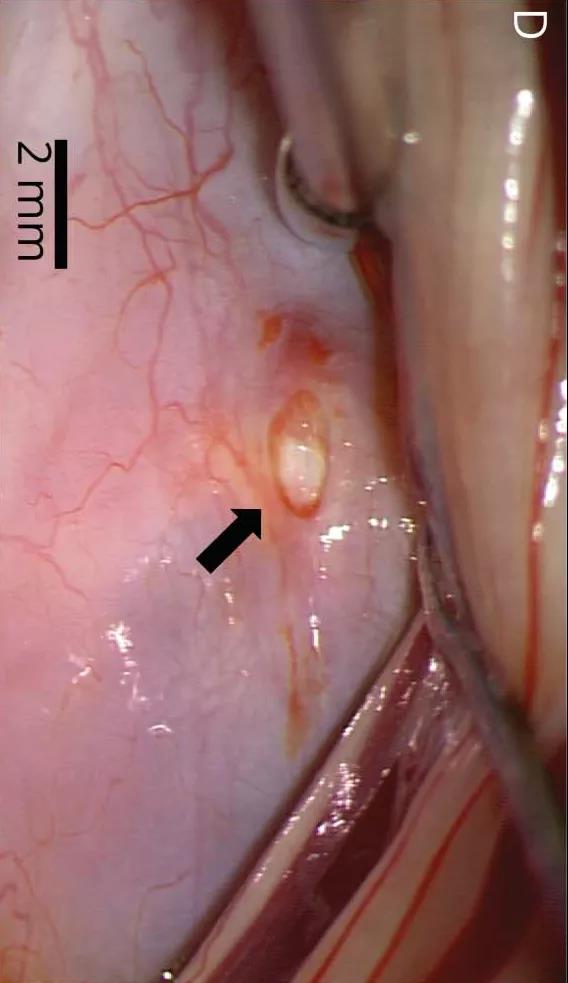

术中照片显示腹侧硬脑膜缺损2 mm(D,箭头):